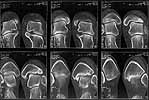

I attach CT of the affected ankle.

Interesting case. thanks for the ct cuts. now it is real clear that there is a posterior medial maleolar fragment displaced into the joint forcing the talus laterally. My first inclination in this young girl is to debride out the displaced fragment. The difficult part will be visualization ot know how much to take. My approach would be through an oblique medial malleolar osteotomy and hinge the distal malleolus away from the talus leaving the deep deltoid intact. this way you could easily view the whole articular surface of the medial gutter. I would debride the prominent bone back slightly beyond the level of the normal malleolar surface. The osteotomy may also help reduce the widened mortise. I don't see anything i would do to the syndesmosis area nor any significant length differences between the fibula and tibia laterally form the proximal tibia fracture.

The CT seems to show residual triplane fx lines.

I wonder if this could have been a 4 part triplane with an intra-medial malleolar component as described by Von Laer JBJSA 67:687 1985 which was displaced by the im device?

John Early's suggestion of posterior medial malleolar debridement and possible medial malleolar repositioning for mortice narrowing is very interesting. You mention that the patient already has mediolateral instability. While it does push the talus laterally, it looks like the posterior medial malleolar fragment may be providing a congruent buttress against medial talar displacement. If that were removed and the mortise was not in some way narrowed - the mediolateral instability might increase.

I wonder if comparison CT cuts of the normal ankle and possibly 3D reconstruction/modeling might give a better understanding of the pathoanatomy.

Today the axial and frontal cuts were performed - attached.

The comparison coronal and axial CT show a tillaux component and a widened mortise which was probably first held open by the im device and then the malunion of posterior medial malleolar fragment - drawn into the joint by the deep deltoid talar attachment.

With posterior medial malleolar fx excision alone, mediolateral instability could increase. The wide mortise, a result of multiplanar fx deformity, needs to be narrowed - but how can this be reliably achieved? Perhaps a 3D model is needed ala

Thanks for the CT. Did she have a higher fibula fracture? I believe she has an external rotation malunion of the posterior malleolus/lateral plafond/ ?fibula. The entire segment displaced laterally and rotationally in relation to the medial malleolus, which stayed home. The talocrual angle is approx the same on each ankle, so I agree the fibula is out to length. I would arthroscope the ankle to visualize the articular surfaces.

The CT scan does seem to identify malunion of the distal tibia, although the exact detail of the fragments and their displacement is not perfectly clear. We think it would be an ideal case for a 3D model.